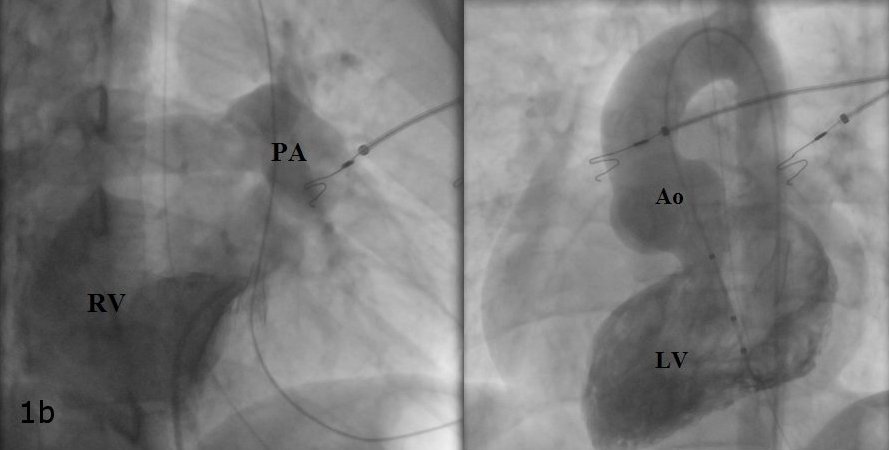

A 19-year-old female underwent repair of complex congenital heart disease (atrial and ventricular septal defect with a criss-cross atrioventricular relationship) in infancy. Because or recurrent palpitations she underwent an electrophysiology study. Atypical atrioventricular nodal reentrant tachycardia was diagnosed. Catheter ablation was performed successfully using cryothermal energy. The diagnostic and therapeutic approach is discussed.